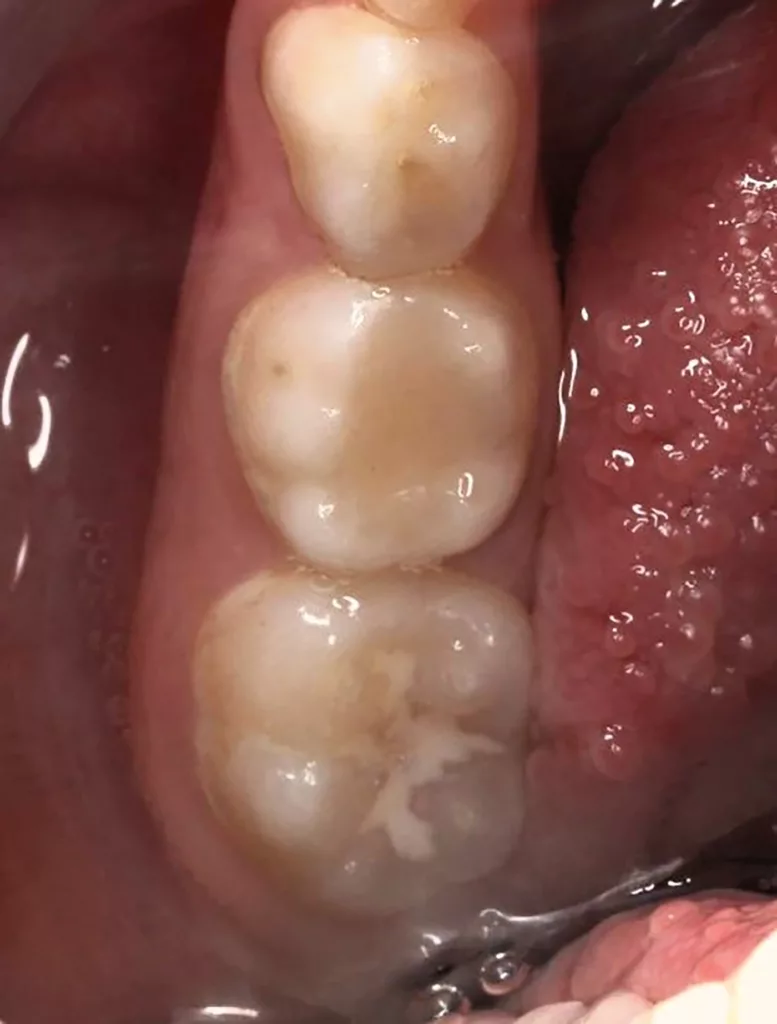

Bei routinemäßigen Röntgenkontrollen ergeben sich manchmal Zufallsbefunde unklarer Genese. So stellt sich beispielsweise bei der Betrachtung der Abbildung 1 die Frage, wie sich ein Zahnhartsubstanzdefekt so schnell entwickeln konnte. Ein weiteres Röntgenbild (Abb. 2), das vor dem Zahndurchbruch aufgenommen wurde, zeigt jedoch, dass es sich in diesem Fall nicht um Karies, sondern um die sogenannte präeruptive intrakoronale Resorption (PEIR) handelt. Für diesen Befund finden sich in der Fachliteratur auch noch andere Bezeichnungen wie „idiopathic external resorption of unerupted permanent teeth“ [1], „intra-follicular caries“ [2], „radiolucent lesions resembling caries“ [3], „occult caries“ [ 4] oder „pre-eruptive caries“ [5].

V. Slabkovskyi, O. LiutikovJahr vor dem Durchbruch des Zahnes 36.

Das fünfjährige Mädchen stellte sich 2017 zur jährlichen Routinekontrolle vor. Im Rahmen der Untersuchung wurden Röntgenaufnahmen der Milchmolaren gemacht (Abb. 2). Der klinische und radiologische Befund der vor uns früher gelegten Kompositfüllungen war gut, es wurde allerdings eine PEIR an den noch nicht durchgebrochenen ersten bleibenden Molaren festgestellt (Abb. 2). Den Eltern wurde empfohlen, sich unverzüglich bei Beginn des Durchbruchs der ersten Molaren erneut zur Behandlung vorzustellen. Ein Jahr später erschien die junge Patientin schmerzfrei zur Kontrolle. Der Zahn 36 war noch teilweise mit Gingiva bedeckt. Auf einer neuen Röntgenaufnahme (Abb. 1) wurde die PEIR-Läsion mit unveränderter Größe in pulpanahen Bereichen bestätigt (Grad 3 der Läsion nach Seow). Der Zahnschmelz sah intakt aus, es konnte kein pathologischer periapikaler Befund bei den noch nicht ausgewachsenen Zahnwurzeln festgestellt werden. Daraufhin wurden die verschiedenen Behandlungsmöglichkeiten von Fissurenversiegelung bis Vitalerhaltung der Zahnpulpa mit den Eltern des Kindes besprochen.